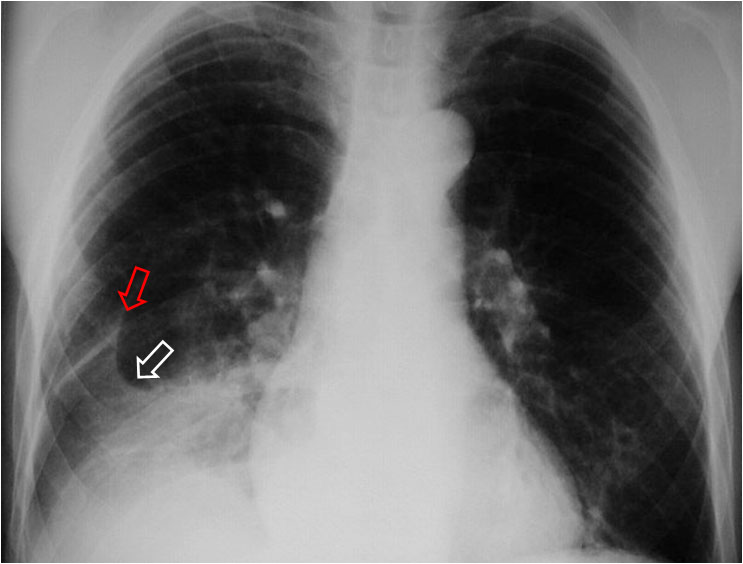

Es un signo de derrame pleural en la cisura mayor visible en la radiografía de tórax, en un paciente con cisura mayor incompleta. Es más frecuente verlo en el lado derecho ya que en el izquierdo la silueta cardiaca puede ocultarlo.

La presencia de una zona radiotransparente perihiliar, circunscrita lateralmente por una línea curva bien marcada (flecha blanca), en cuya periferia se observan varios grados de opacidad, corresponde a la presencia de líquido en la cisura mayor incompleta. La línea curva termina en un extremo en punta (flecha roja), que estará más cercana al hilio cuanto más completa sea la cisura.

El nombre de pseudocavidad hace referencia a la radiolucencia perihiliar, mientras que el de espina de la rosa se refiere a la morfología de la opacidad, con el extremo en punta.